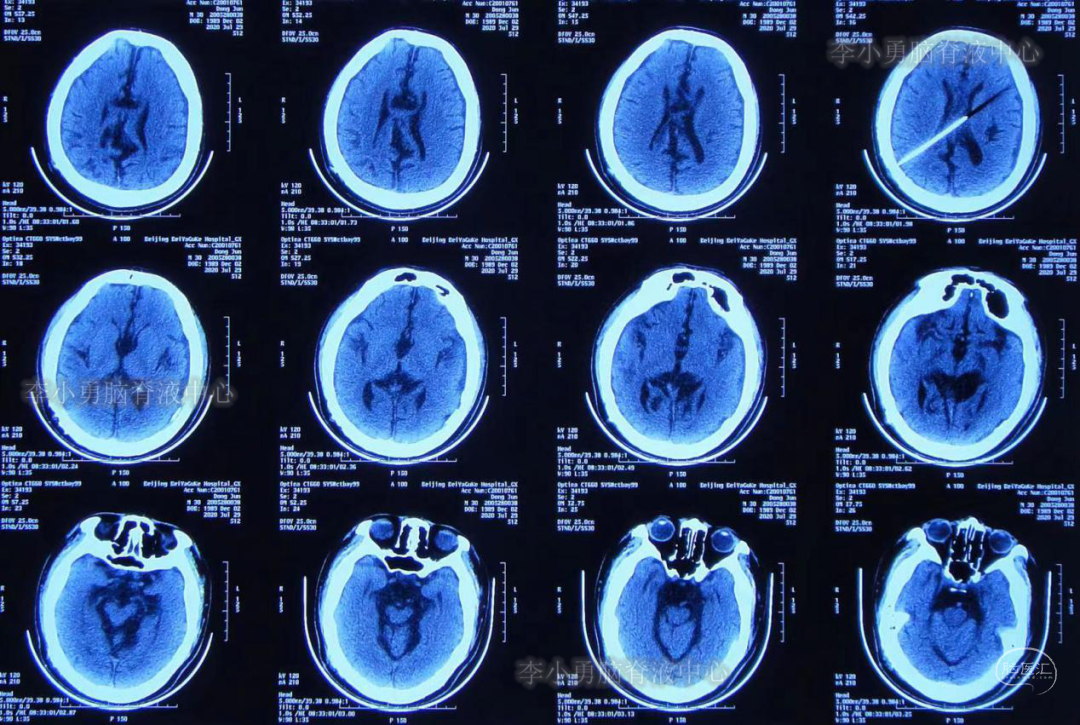

入院后第4天即2020年6月1日,行原脑室腹腔分流管拔除术+脑室外引流术,术后当日复查头部CT(图-5)。

图-5:2020年6月1日术后头CT

脑室外引流术后第3天即2020年6月4日,复查头部CT(图-7)见脑室系统较前缩小。

图-7:2020年6月4日头CT脑室系统较前缩小